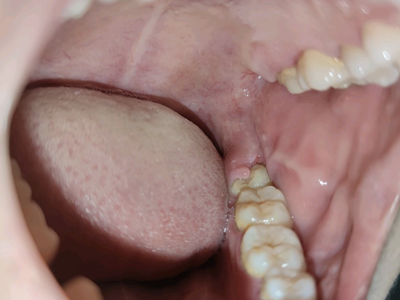

阻生牙是指由于邻牙、骨或软组织的阻碍而只能部分萌出或完全不能萌出,且以后也不能萌出的牙。引起牙阻生的成因,主要是由于颌骨缺乏足够的空间容纳全部恒牙。常见的阻生牙为下颌第三磨牙、上颌第三磨牙及上颌尖牙。

阻生牙可反复引起冠周炎,或引起邻牙牙根吸收和破坏,位置不正,不能完全萌出,好发部位是上、下颌第三磨牙。